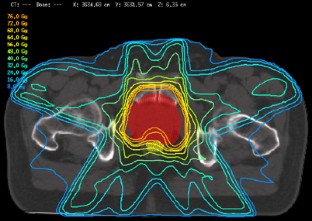

Abb. 3